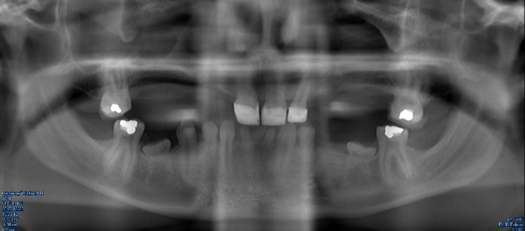

Fig 9. Panoramic radiograph, 25-year-old brother.

Figure 9

Figure 5 through Figure 12 exemplify what currently may present in private dental practices with these types of patients. Four brothers aged 14 years to 27 years all suffered from obstructed airways; high incidence of caries of dentin, enamel, and cementum; moderate periodontal disease; collapsed vertical; undiagnosed OSA; and the potential for increase in comorbidities such as diabetes, cardiovascular disease, dementia, cancer, high blood pressure, and others. Symptomology was presented throughout the young lives of the brothers in this family. The parents were unaware that the dental agenesis and premature permanent tooth extraction could have led their sons into severe health issues as they matured.